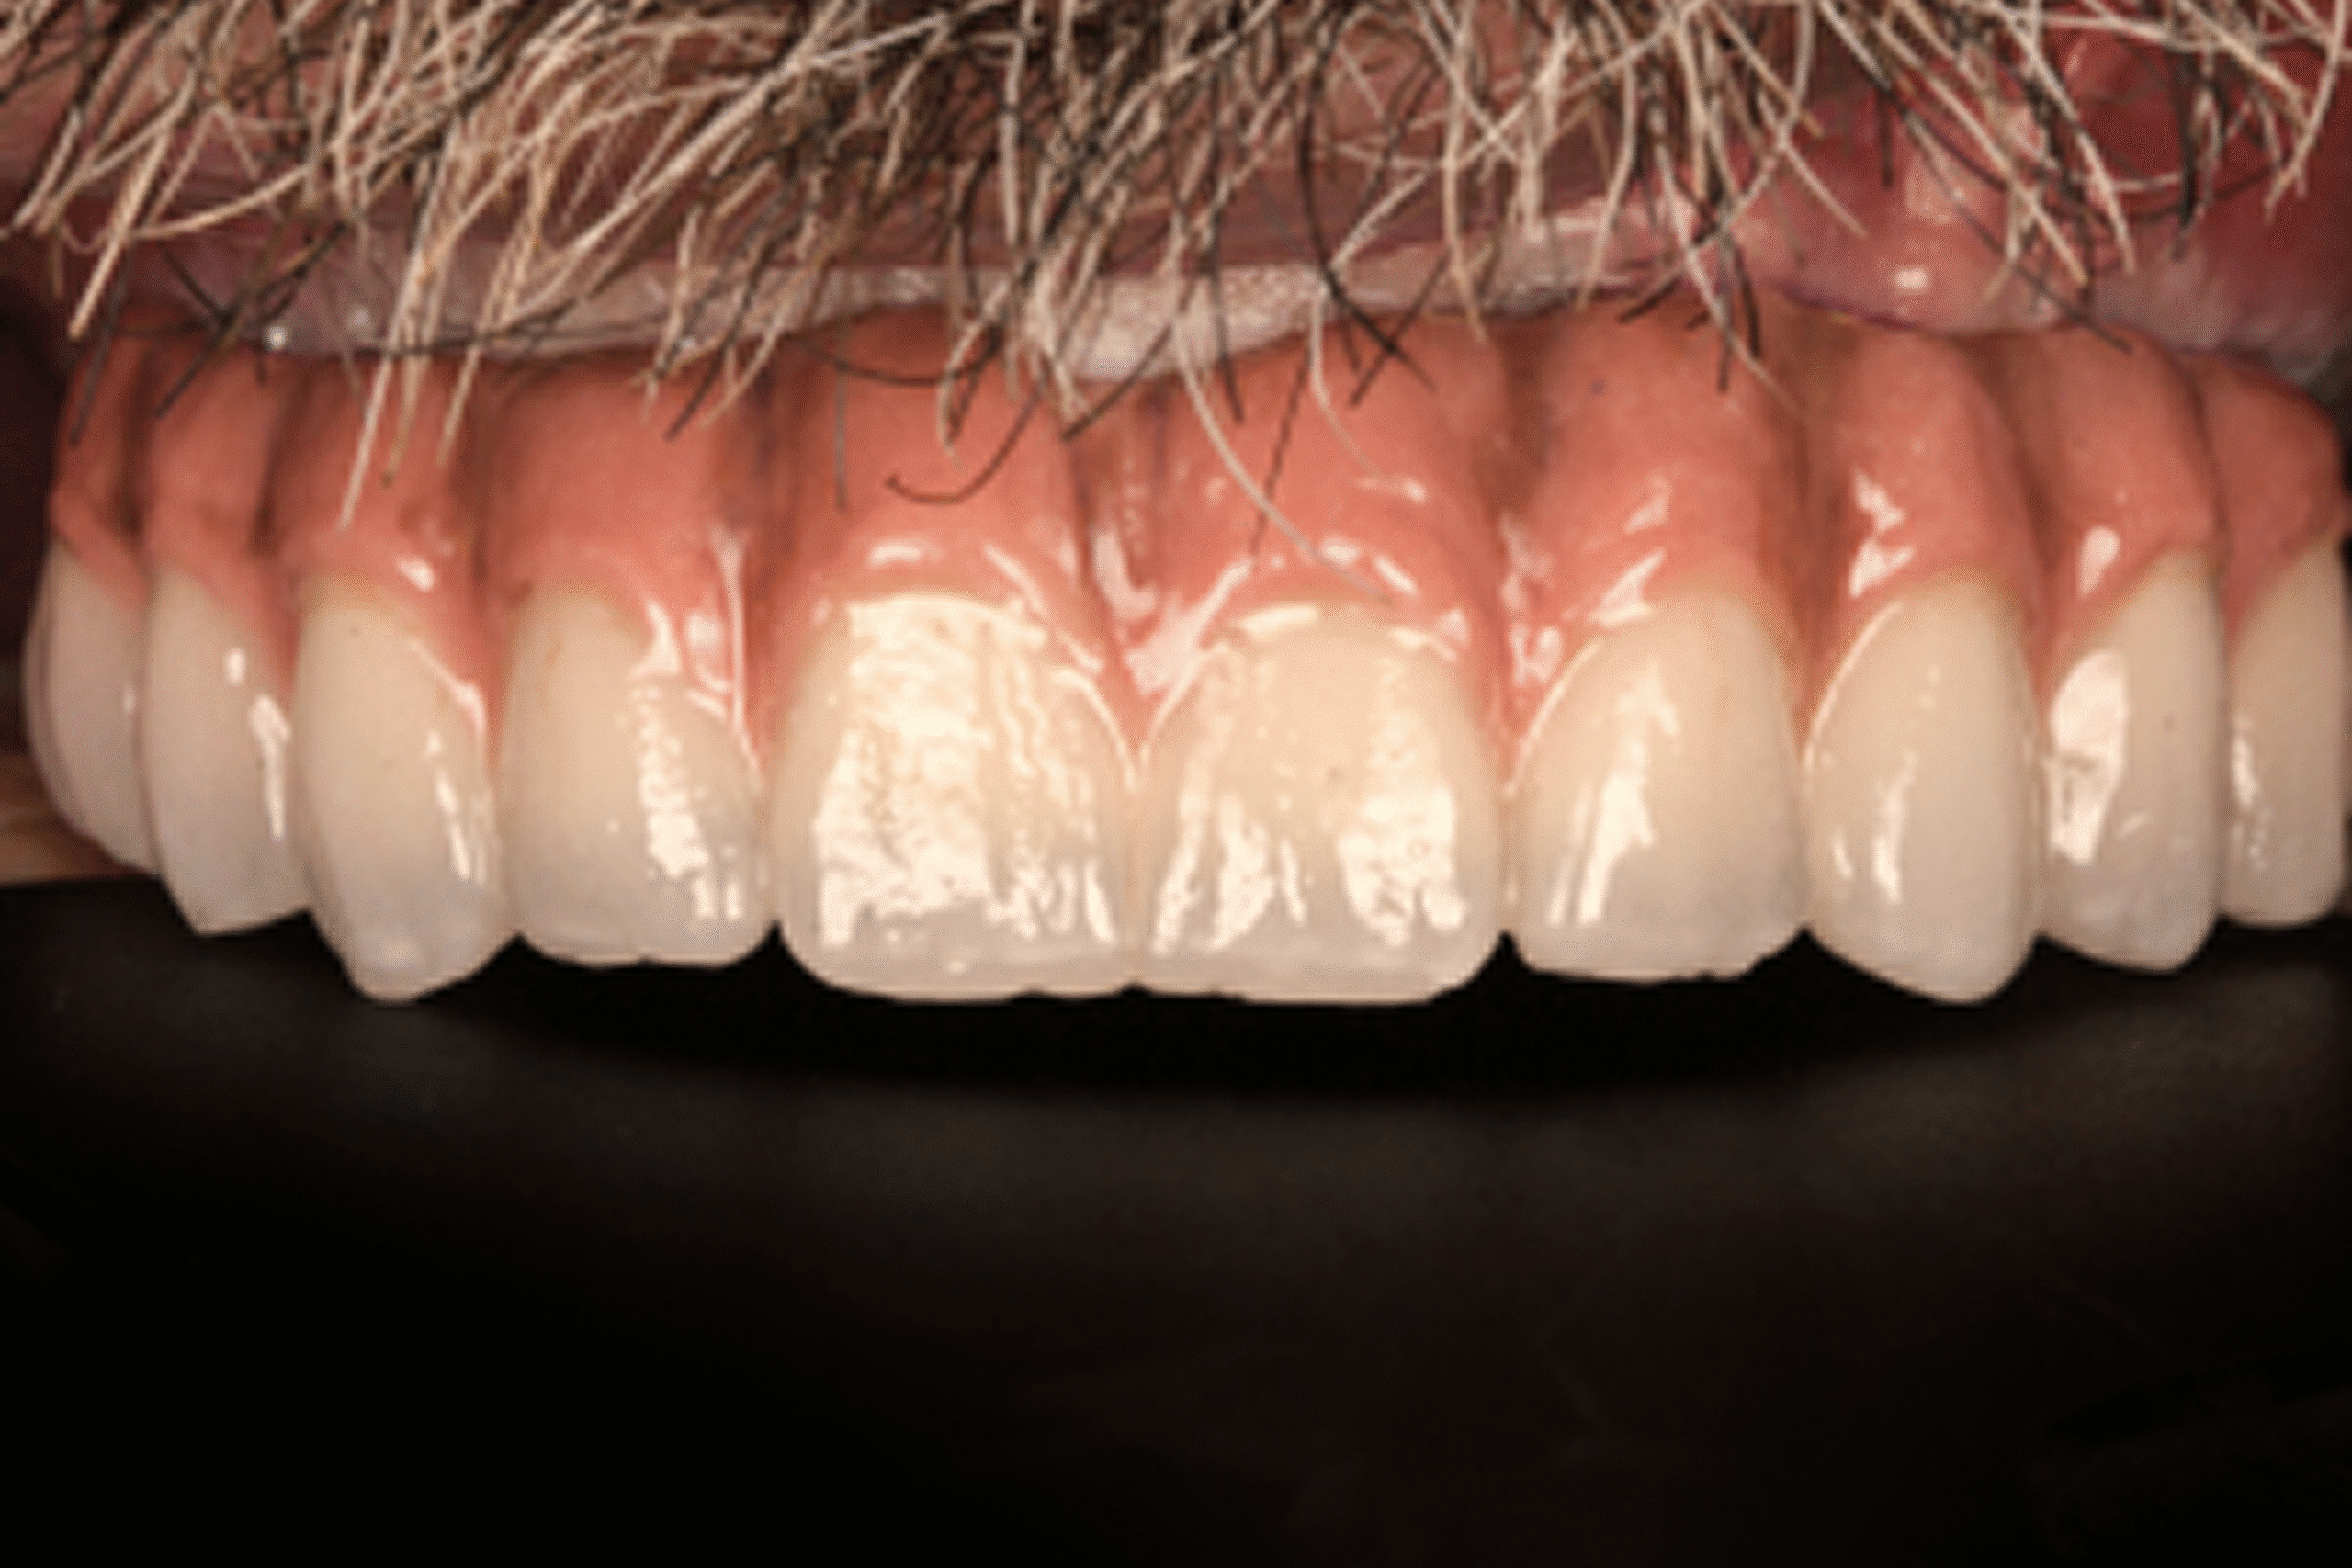

After

Day 10 — Delivery of Immediate Fixed Prosthetics

- Secure fitting of temporary full-arch restoration

- Immediate improvement in stability, speech, chewing function, and smile aesthetics

Within 10 days, he transitioned from a failing, painful situation to a stable, functional, and natural-looking full-arch restoration supported by only four well-positioned implants.